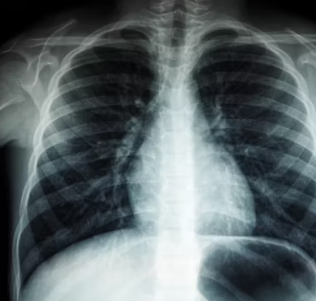

천식은 기관지에 만성적인 염증이 생겨 기관지가 좁아지고 예민해지는 질환입니다. 기침, 숨가쁨, 쌕쌕거리는 숨소리 등의 증상이 반복적으로 나타나며, 심하면 호흡 곤란으로 응급 상황이 발생할 수도 있습니다. 40대 이후에도 새롭게 발생하거나 기존 증상이 악화될 수 있어 관리가 중요합니다.

이 글에서는 천식이 왜 발생하는지, 놓치지 말아야 할 초기 증상은 무엇인지, 그리고 천식을 예방하고 관리하기 위해 어떤 노력을 해야 하는지 자세히 정리해 보겠습니다.